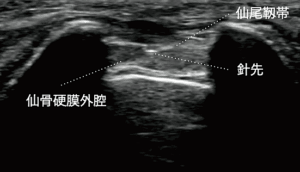

仙骨裂孔硬膜外神経ブロック

腰臀部の痛みや下肢の神経痛が強いときに行う神経ブロック治療です。

主に腰部椎間板ヘルニア・腰部脊柱管狭窄症に対して行います。罹患神経周囲に薬剤が届き神経の炎症や痛みの悪循環をブロックします。数回やっても効果の少ないときは中止します。ブロック後20~30分休んで頂きます。

超音波ガイド下で刺入